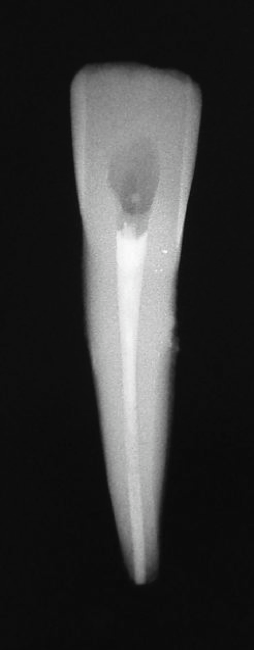

Fig 2. Minimal walls.

Figure 2

Figure 2 shows a situation where the clinician excavated the tooth of a patient with decay, and it pulped out. The buccal and lingual walls were intact; however, the walls were minimal, and there were still fragments of amalgam and cracks. If the clinician prepared this tooth after building it up, the clinician would lose all the good tooth structure that was left. This tooth would likely need a post.